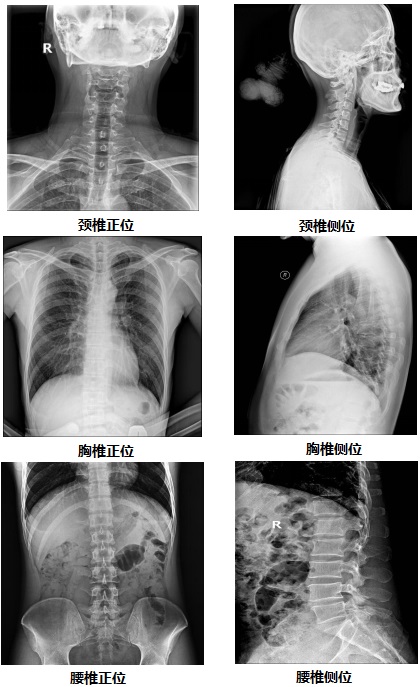

【固定悬吊dr-PLD7800E部分临床效果图】